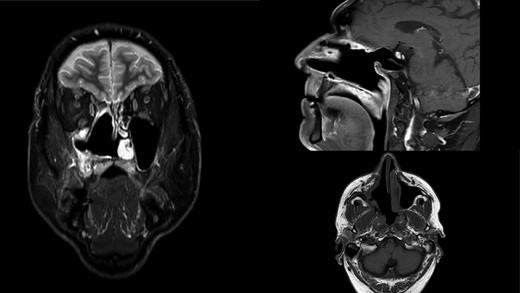

The final histopathology corresponded to the biopsy findings. Due to the lack of accurate diagnosis, molecular pathological analysis of all available EWS FLI1 and EWS ERG fusion genes by polymerase chain reaction method was performed and the result was negative. Furthermore, no redistribution of the EWSR1 gene was found by the FISH method, and MDM2 was poorly amplified in 2% of tumor cells, which would exclude the diagnosis of Ewing’s sarcoma. Samples were also sent for consultation and review to the other three Pathology Clinics. Their histopathological findings corresponded to a poorly differentiated high-grade pleomorphic sarcoma with elements indicating bone differentiation and diagnostically corresponded to osteosarcoma, but without definitive diagnosis. The patient was presented again to the board for mesenchymal malignancies and a decision on adjuvant radiotherapy was made. The patient received 60 Gy of radiotherapy in 30 fractions and was free of tumor 14 months postoperatively (Fig. 3). One month later, the patient noticed a small nodule in the right parotid gland. An ultrasound-controlled fine-needle biopsy was performed. The biopsy finding, as well as definitive histopathology diagnose performed after superficial parotidectomy, corresponded to a pleomorphic adenoma.

MR scan in coronal, sagittal and axial view on control 14 months postoperatively. Right nasal cavity and right maxillar sinus and ethmoid widely open free of tumor.